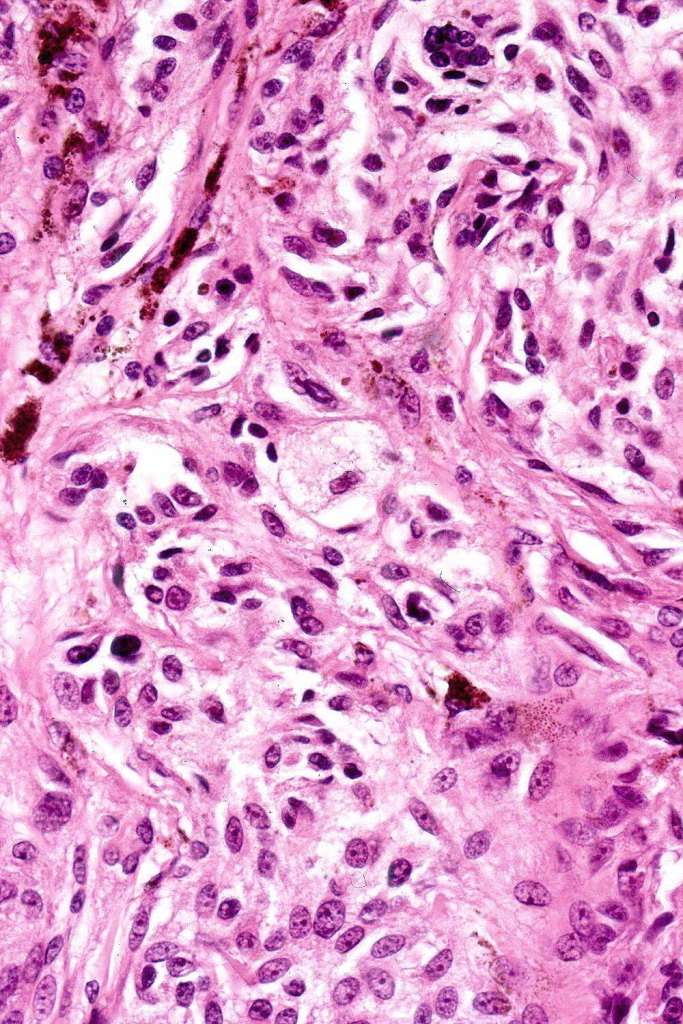

•Focal atypia (enlarged, hyperchromatic nuclei)

•Clear cells

•Dendritic cells

•Melanophages

•Multinucleate giant cells

• Cytoplasmic intranuclear pseudo-inclusions, small eosinophilic nucleoli

•Occasional mitoses

Atypical features which may be encountered include marked nuclear pleomorphism, conspicuous mitotic activity, atypical mitoses (atypical or borderline lesion)- may be associated with lymph node involvement although frank maliganncy is exceptional